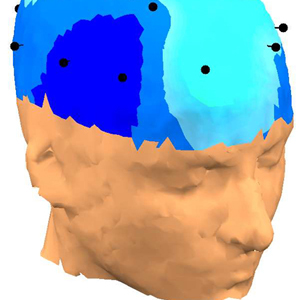

ȣȯ °¡´ÉÇÑ Á¦Ç° ¹®ÀÇÇϱâde-artifacted EEG´Â 󸮵Ǿî qEEG-Pro µ¥ÀÌÅͺ£À̽ºÀÇ °ü·Ã ¿¬·É´ë¿Í ºñ±³µË´Ï´Ù. sLORETA¸¦ »ç¿ëÇÏ¿© Linked Ears ¸ùŸÁÖ, Laplacian (CSP) ¹× ¼Ò½º À籸¼º ½ÅÈ£¿¡ ´ëÇÑ 3 °¡Áö pdf º¸°í¼°¡ ÀÛ¼ºµË´Ï´Ù. qEEG-Pro º¸°í¼´Â ´ÙÀ½°ú °°Àº ºÐ¼®À¸·Î ±¸¼ºµË´Ï´Ù.

• FFT Absolute Power (°í¼ÓǪ¸®¿¡º¯È¯ Àý´ë Àü·Â)

• FFT Relative Power (°í¼ÓǪ¸®¿¡º¯È¯ »ó´ë Àü·Â)

• Phase Coherence (À§»ó Àϰü¼º)

• Alpha peak detection (¾ËÆÄ ÇÇÅ© °ËÃâ)

• Amplitude Asymmetry (ÁøÆø ºñ´ëĪ)